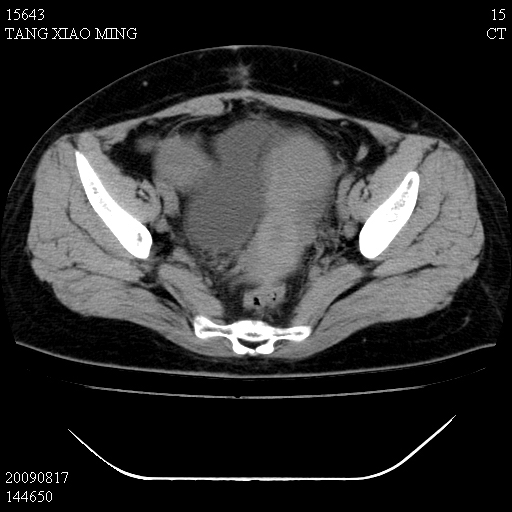

标题: CT21692:盆腔病变

女,33岁,右下腹痛2年余,既往宫外孕病史,如在我院手术,结果下周公布,

可能的诊断。1子宫内膜异位【子宫腺肌症并右卵巢巧克力囊肿】;2 右卵巢囊腺瘤。子宫肌瘤

1)考虑卵巢巧克力囊肿,不排除卵巢囊腺瘤。2)子宫肌瘤可能。

卵巢囊腺瘤,子宫肌瘤,直肠壁厚,不除外占位.